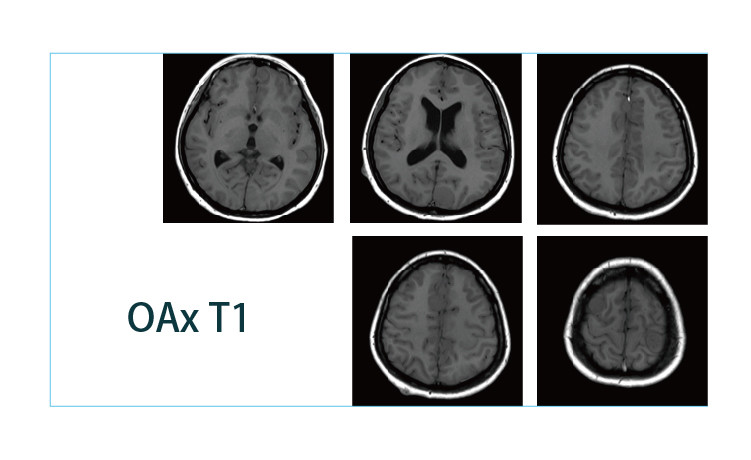

【朗润影像档案】磁共振影像病例分享(编号20190412)

2019-04-25 17:22:57